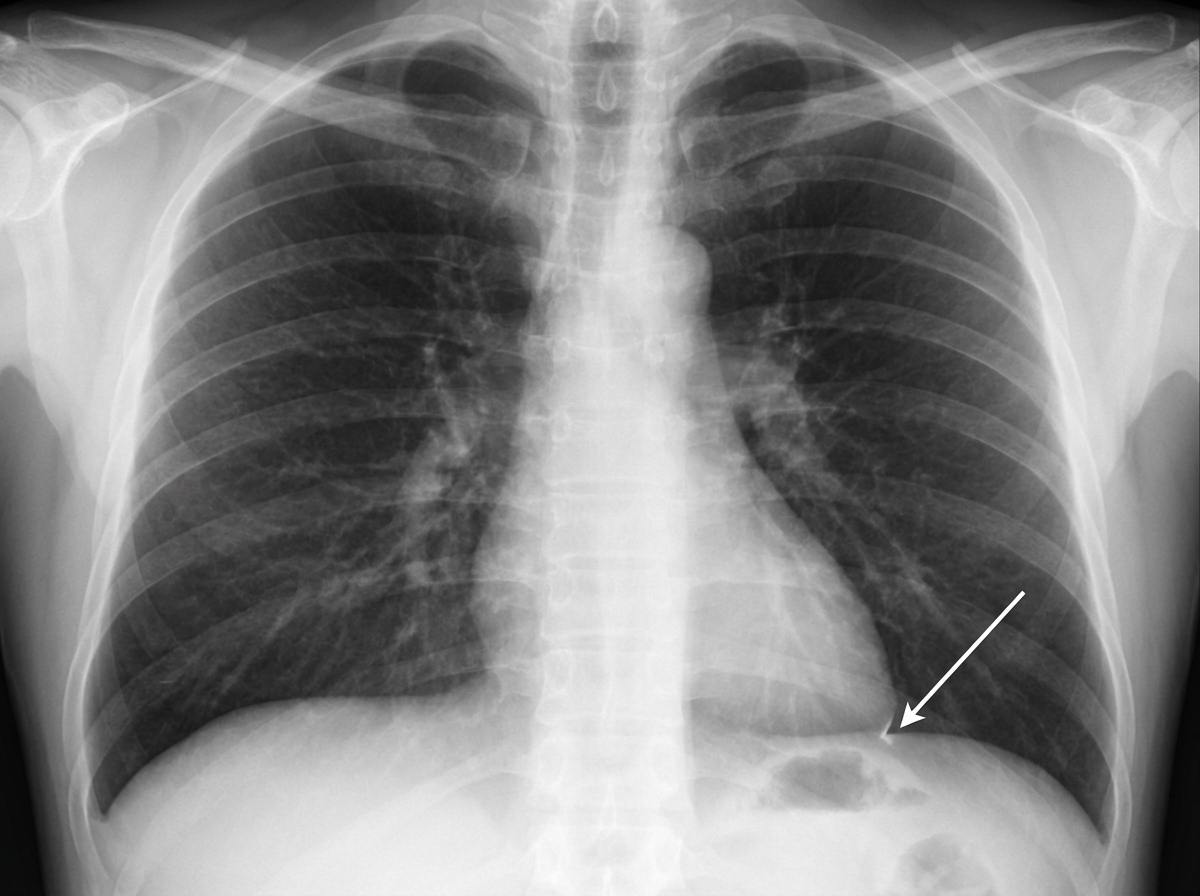

Identify the structure indicated in the given chest X-ray.

Explanation: ***Left-Cardiophrenic angle*** - The **left-cardiophrenic angle** is formed by the junction of the **left heart border** and the **left hemidiaphragm**, creating a sharp, acute angle. - It is located more **medially** compared to the costophrenic angle and represents the **cardiac silhouette's** interface with the diaphragm. *Left-Costophrenic angle* - The **left-costophrenic angle** is formed by the junction of the **left hemidiaphragm** and the **lateral chest wall** (ribs), not involving the heart border. - It is located more **laterally** and represents the **pleural space** where fluid collections (pleural effusions) are first detected. *Right-Costophrenic angle* - The **right-costophrenic angle** is located on the **opposite side** of the chest from the indicated structure. - It is formed by the junction of the **right hemidiaphragm** and the **right lateral chest wall**, appearing as a sharp angle laterally. *Right-Cardiophrenic angle* - The **right-cardiophrenic angle** is located on the **opposite side** of the chest from the indicated structure. - It is formed by the junction of the **right heart border** and the **right hemidiaphragm**, positioned medially on the right side.